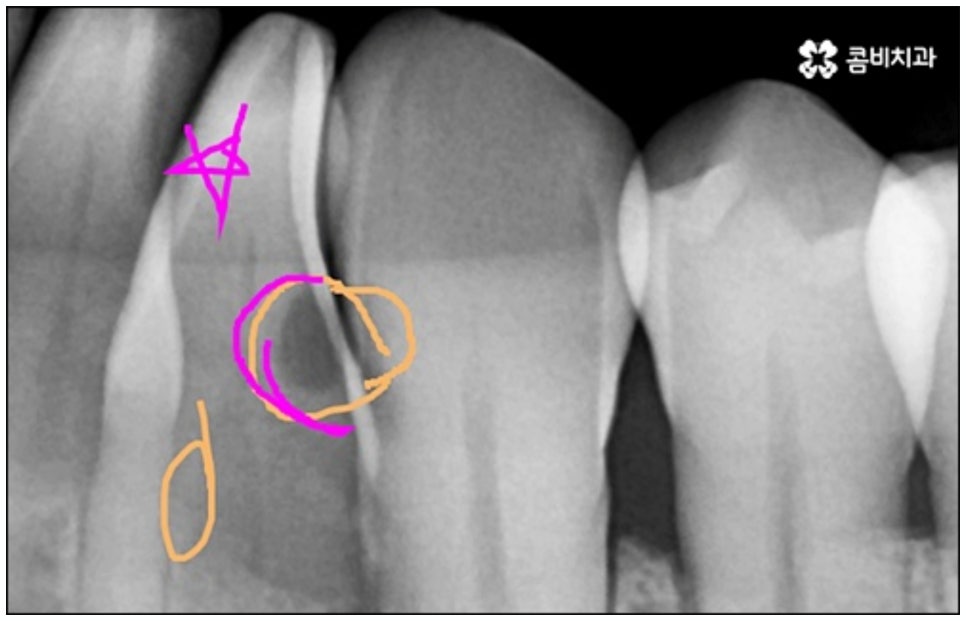

예를 들어서 오랜 치주염으로 퇴축이 진행되어 잇몸이 이미 많이 내려앉은 경우, 심한 치아 뿌리 염증으로 잇몸뼈가 상당부분 녹은 경우, 노화나 지병으로 인해 골밀도가 낮고 잇몸뼈가 약해져 지지가 어렵거나 쉽게 부서지는 등 뼈의 상태가 양호하지 못한 경우 등에 있어서는 발치 후 즉시 임플란트를 식립하는 방식이 적합하지 않으며 치아가 한꺼번에 여러개 손상된 경우에도 6~8주 정도의 시간을 두고 무리하지 않게 단계적으로 식립하는 것이 혹시 모를 부작용을 막고 장기적인 안정성을 높이는 방법이라고 할 수 있어요.